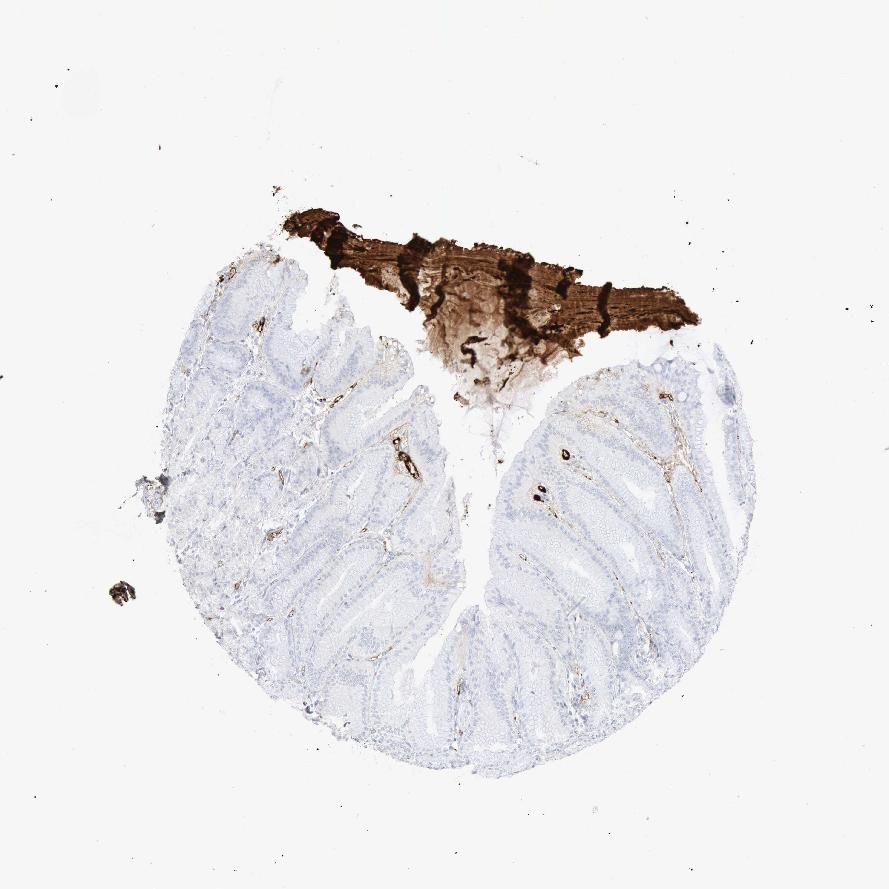

STOMACH 2 - Antibody stainingi

Antibody staining in the annotated cell types in the current human tissue is reported as not detected, low, medium, or high, based on conventional immunohistochemistry profiling in selected tissues. This score is based on the combination of the staining intensity and fraction of stained cells.

Each image is clickable and will lead to virtual microscopy that enables deeper exploration of all samples and also displays staining intensity scores, fraction scores and subcellular localization as well as patient and tissue information for each sample.

Antibody HPA000926Antibody HPA001578

Glandular cells LowNot detected